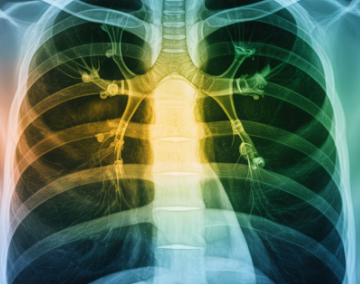

폐암은 조기 발견이 무엇보다 중요한 질환이지만,

초기에는 특별한 통증 없이 조용히 진행되는 경우가 많습니다.

1. 폐암이 초기 증상이 적은 이유

폐 조직에는 통증을 느끼는 신경이 거의 없어,

종양이 자라더라도 초반에는 큰 불편함이 나타나지 않습니다.